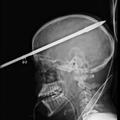

Slovenija Glavo mu je preluknjala harpuna Šestnajstletnik čudežno preživel strel v glavo s harpuno. Posledic ne bo imel.